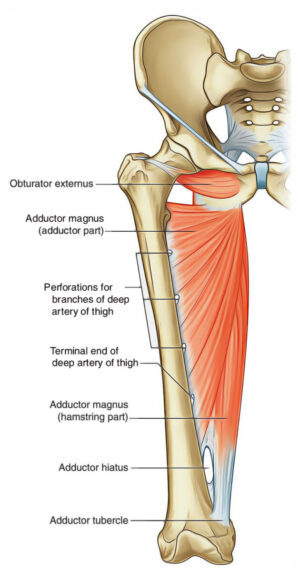

Анатомия и Функции Мышцы Adductor Magnus